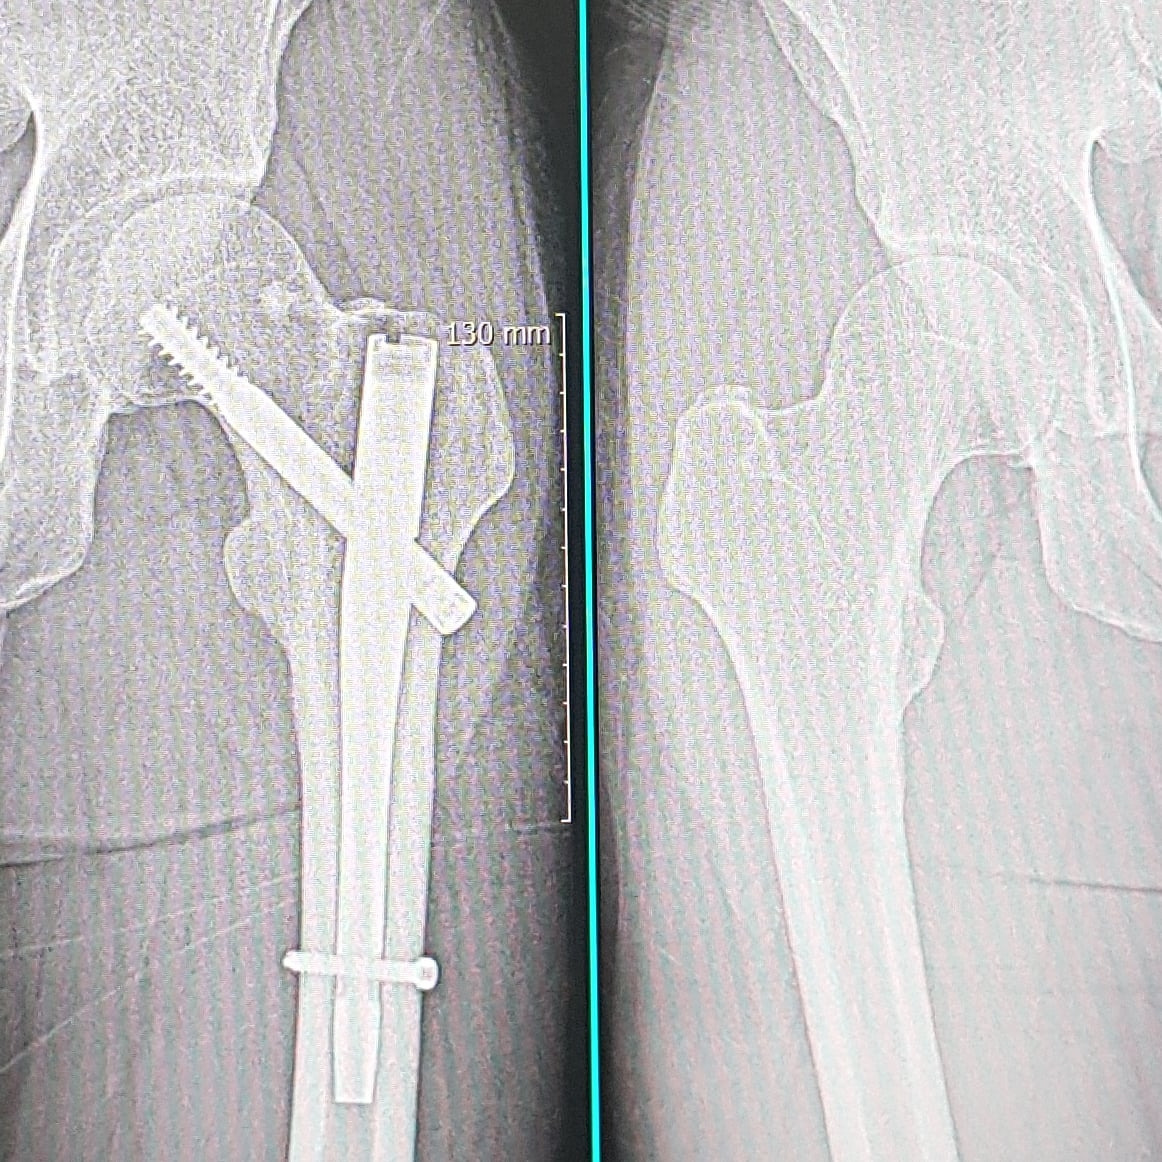

자전거 낙차 사고로 고관절이 부러졌다.

수술 후 거의 한 달 시점인 오늘 병원에 가서 X-ray 촬영을 했다.